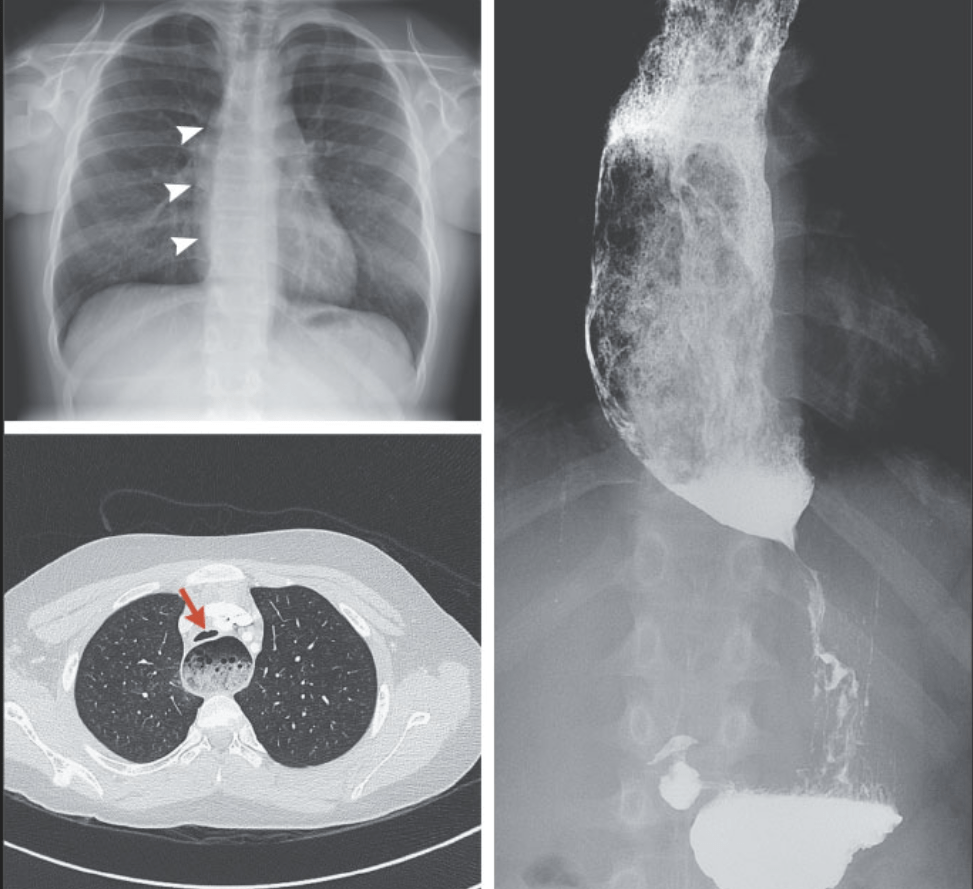

S Woodhull, DR Segar N Engl J Med 2021; 385:e64. DOI: 10.1056/NEJMicm2108193